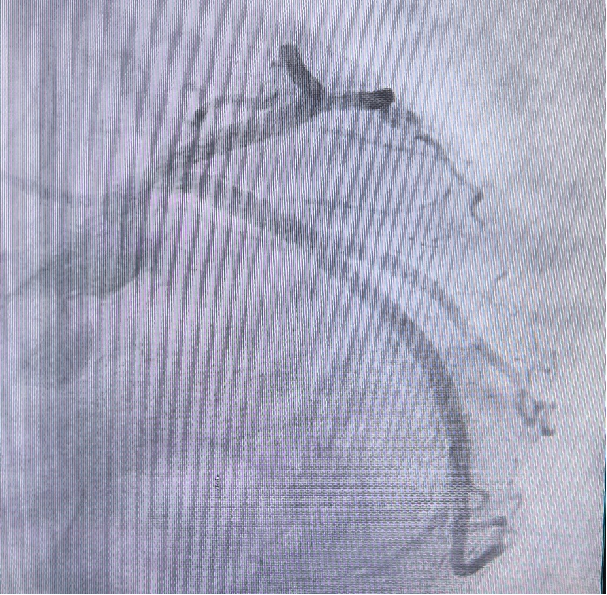

外院 CTA 提示左主干中度狭窄。

冠脉CTA(外院):LM 中度狭窄(阅片见 RCA 开口重度狭窄)。

左主干、前降支 轻度狭窄。 右管开口局限偏心 90% 病变。